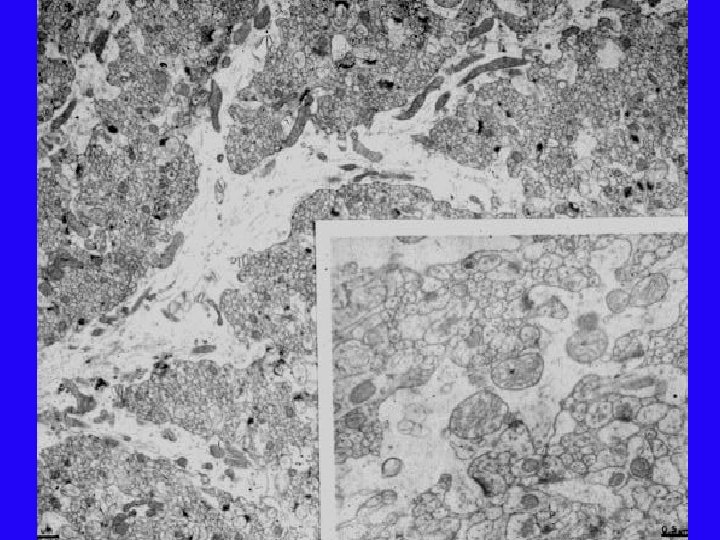

Rehabilitation Condition

Inactive Condition